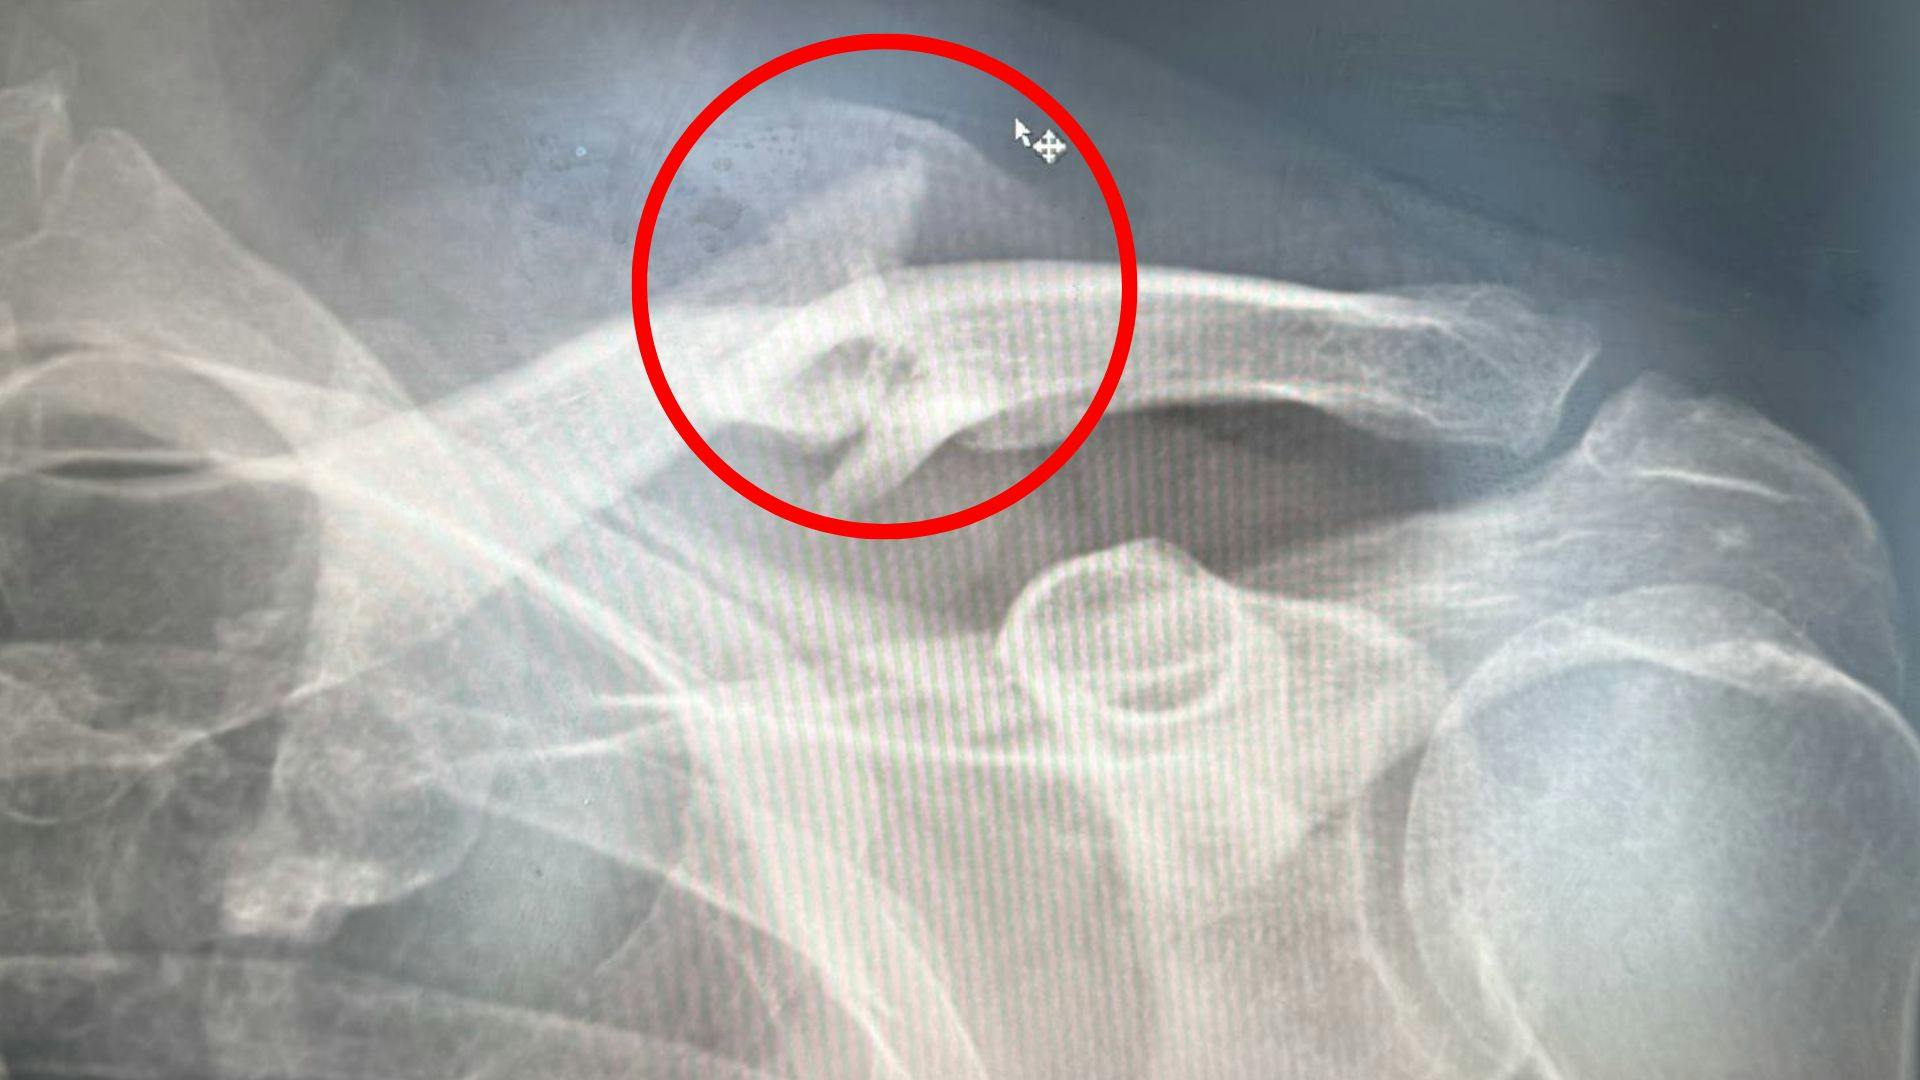

LÆS OGSÅ: Claus Elming i voldsomt styrt: Brækket kraveben, ribben og flænge i skulderbladet

- Kravebenet er brækket flere steder og er bare groet lidt skævt sammen. Så jeg har konstante smerter. Så nu tager jeg operationen på tirsdag.